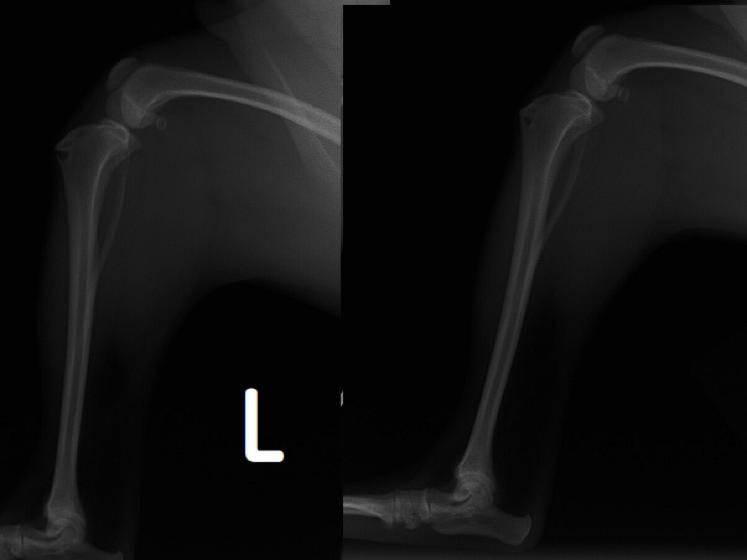

■ 症例20 ポメラニアン 8ヶ月 1.8kg

左右膝蓋骨脱臼 グレードⅢ

2ヶ月前から間欠的跛行が認められ、両膝の膝蓋骨脱臼整復術を行った。

手技は縫工筋及び内側広筋の解放、脛骨粗面の外側転位、滑車ブロック形造溝術、内外側関節包の縫縮を選択し実施した。

右側の膝蓋骨脱臼は上記手技で整復されたものの、左側はそれのみでは膝蓋骨が浮く様子が認められた。その為、PDS縫合糸にて膝蓋靱帯を1糸のみ縫合し、靱帯の縫縮を行った。

膝蓋骨脱臼は膝関節における膝蓋骨の内外側の脱臼と定義されるが、時として単純な内外の脱臼ではなく、膝蓋骨が大きく前方に浮き上がるように脱臼する場合がある。特にトイプードルやポメラニアンといった犬種に多く認められる。

内側脱臼に加えて前方への浮き上がりを矯正する為に、従来より脛骨粗面転移により膝蓋靭帯を外方と下方に引っ張り、固定する方法を選択する。膝蓋骨の前方への浮き上がりが軽度の場合は、従来法ではなく関節包の縫縮で対応していた。しかし、一部の症例で膝蓋骨の動きが悪くなり伸展機構が円滑に機能せずロボット様歩行になるケースがあった。

その為、膝蓋靭帯自体を縫縮する方法を採用した。この方法により、膝関節の伸展機構を妨げず膝蓋骨の軽度の浮きを矯正することが可能となった。

本症例の経過は良好である